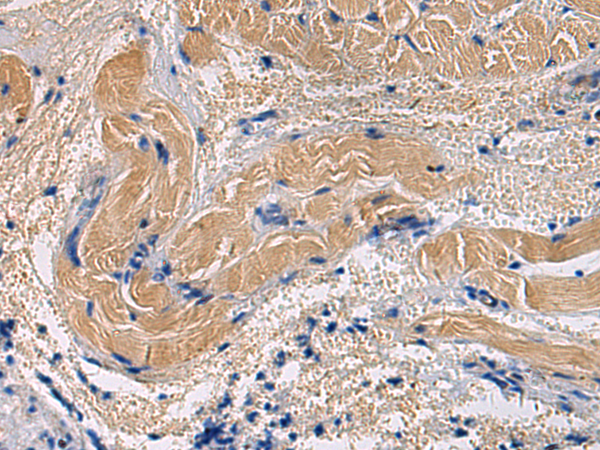

分类: 科研抗体货号: P13460别名: LGP1; D11LGP1应用: IHC反应种属: Human